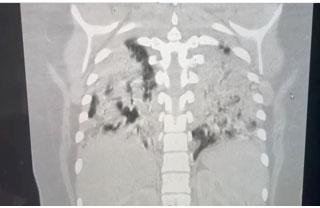

Imaging

Diagnosis of LUTO is accurately done through ultrasound with high sensitivity and specificity [28]. Lower urinary tract obstruction may present in fetuses with a dilated renal pelvis and small fluid filled areas (Figure 11). Distinctions between obstructive and non-obstructive causes can be made through echogenicity and presence of oligohydramnios [29]. Obstructions may present with a large bladder (megacystis) and dilation of urethra (“keyhole sign”) depending on location of obstruction [30]. If anhydramnios is noted on ultrasound it is associated with a higher prevalence of pulmonary hypoplasia and renal dysplasia [28]. Changes in renal parenchyma on ultrasound are also associated with a higher rate of renal dysplasia [28]. Magnetic resonance imaging is suggested if ultrasound cannot be used for assessment of genitourinary tract because of oligohydramnios. Fetal serial urine analysis will be helpful in understanding renal function and provide further information for prognosis.

It is important in diagnosis to visualize the bladder and kidneys assessing for any abnormalities. Identifying specific obstruction will be key in prognosis and consideration for surgical intervention (Figure 11).

Figure 11: Ultrasound image of a LUTO anomaly showing an enlarged fetal bladder (B) with a dilated proximal urethra (u) [43]. Radiological images were obtained from open-access article distributed under the terms of the Creative Commons Attribution License (CC BY) [43].